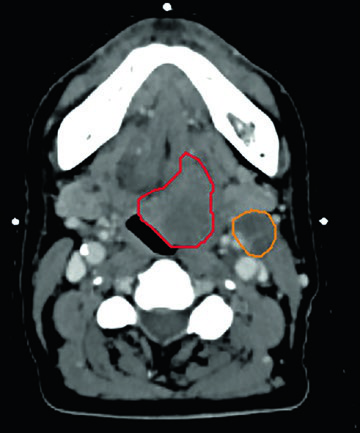

Unresectable piriform sinus tumor. A 73-year-old woman with T1N3 squamous cell carcinoma of the left piriform sinus compressing the internal jugular vein elected against a protracted radiation course. She received 50 Gy in 5 fractions to the GTVn (nodal volume, orange) and 40 Gy in 5 fractions to the GTVp (primary volume, red), twice weekly. Target coverage was not compromised to spare the carotid artery — consistent with the recommendation that the carotid should not limit target dose in the non-re-irradiated setting. At 2 years, no evidence of disease.